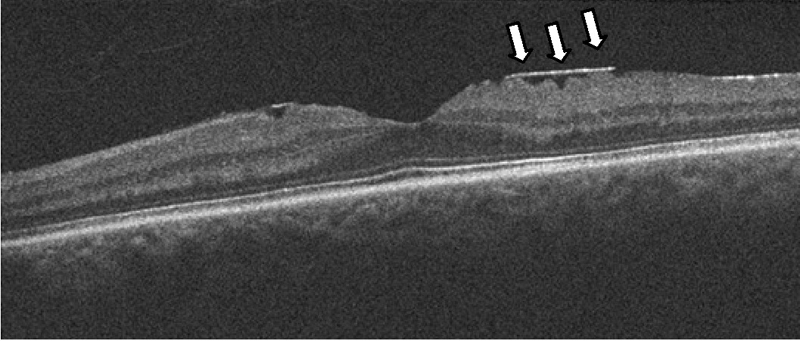

Otro subgrupo en el que puede objetivarse el cierre espontáneo es el de los agujeros maculares traumáticos. Según la serie estudiada

13,14, entre un 10% y un 40% de estas lesiones pueden cursar con cierre en los primeros 3 meses (

Figura 10), aunque en ocasiones este se acompaña de una atrofia de la retina secundaria al traumatismo. Los agujeros maculares traumáticos presentan unas particularidades respecto a los idiopáticos

15: suelen ser más delgados y no asocian signos de cronicidad (como edema quístico), son de base más ancha e irregulares, y en muchos casos persiste la adherencia de la hialoides posterior. Se han propuesto varios patrones por OCT sin que se hayan relacionado con pronóstico visual

16.

Figura 10. Cierre espontáneo de agujero macular traumático. Se aprecia en la retinografía el edema del polo posterior. En la tomografía inicial se objetivan las particularidades de estos agujeros: son más anchos en la base, no suelen asociar signos de cronicidad ni edema quístico y habitualmente son irregulares.